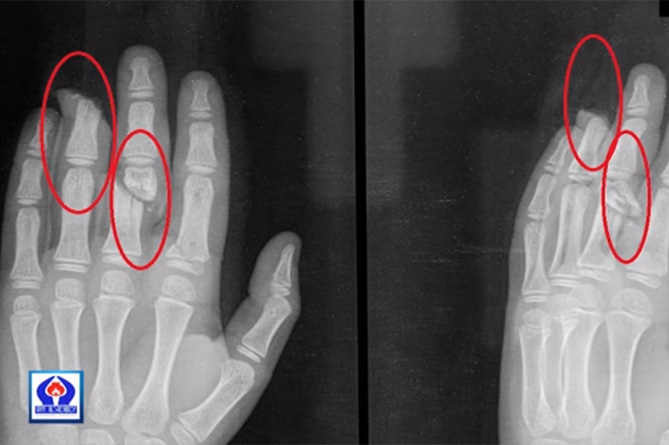

ԵՐԵՎԱՆ, 10 դեկտեմբերի./Նովոստի–Արմենիա/. 8 տարեկան երեխան փայտ է կոտրել ու վնասել 2 տարեկան եղբոր մատները:

Այս սեզոնին ավելացել են անդամահատված մատների դեպքերը:

Վերջին շրջանում «Սուրբ Աստվածամայր» ԲԿ են ընդունվել նույնանման դեպքերով մի քանի երեխաներ:

Պլաստիկ վիրաբույժ Արթուր Հարությունյանը խոսել է դեպքերի մասին ու ցույց տվել թե ինչ պետք է անեն ծնողներն այդ իրավիճակում:–0–